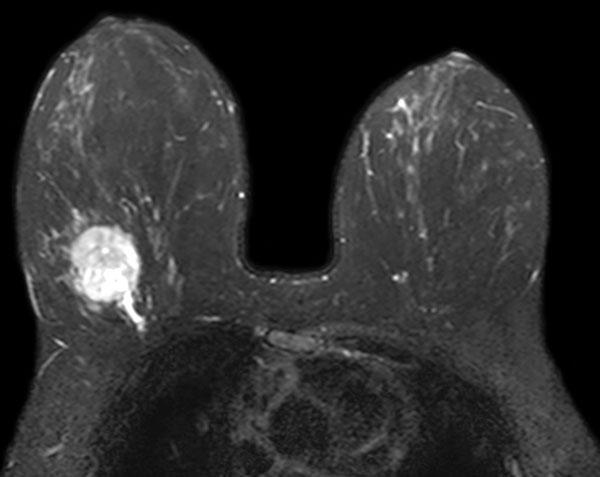

Ressonância Magnética Mamária

A Ressonância Magnética Mamária é um exame altamente sensível utilizado para detetar alterações nas mamas, especialmente em situações em que outros métodos de imagem, como a mamografia ou ecografia, não são conclusivos. É particularmente útil em mulheres com elevado risco de cancro da mama, mamas densas ou em contexto de acompanhamento pós-tratamento oncológico.

A Ressonância Magnética Mamária é um exame de imagem que utiliza campos magnéticos e ondas de radiofrequência para obter imagens detalhadas dos tecidos mamários. Ao contrário da mamografia, não utiliza radiação ionizante.

A Ressonância Magnética Mamária não substitui a mamografia e a ecografia mamária, mas é um exame complementar em situações especiais, tais como o diagnóstico e avaliação da extensão local do cancro da mama, monitorização da quimioterapia ou avaliação de próteses mamárias.

Na Ressonância Magnética Mamária é administrado contraste paramagnético endovenoso, pelo que será necessário puncionar o seu braço ou mão para cateterizar uma veia periférica. É um contraste não iodado e não radioativo que, pela sua distribuição no tecido mamário, ajuda a identificar melhor potenciais lesões/tumores.